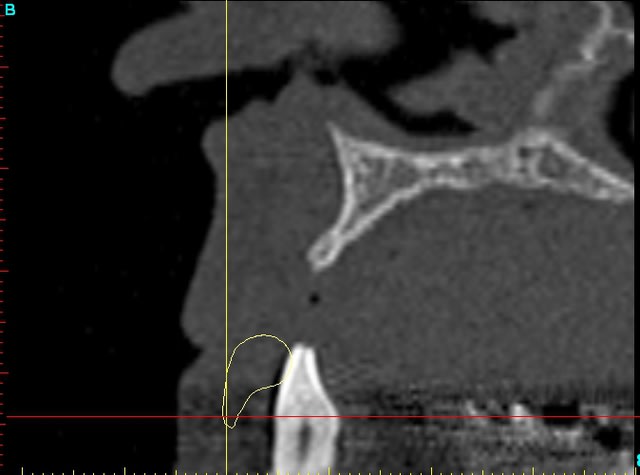

Dar13 snfr77 - Eugenol

13dar zaa5vz - Eugenol